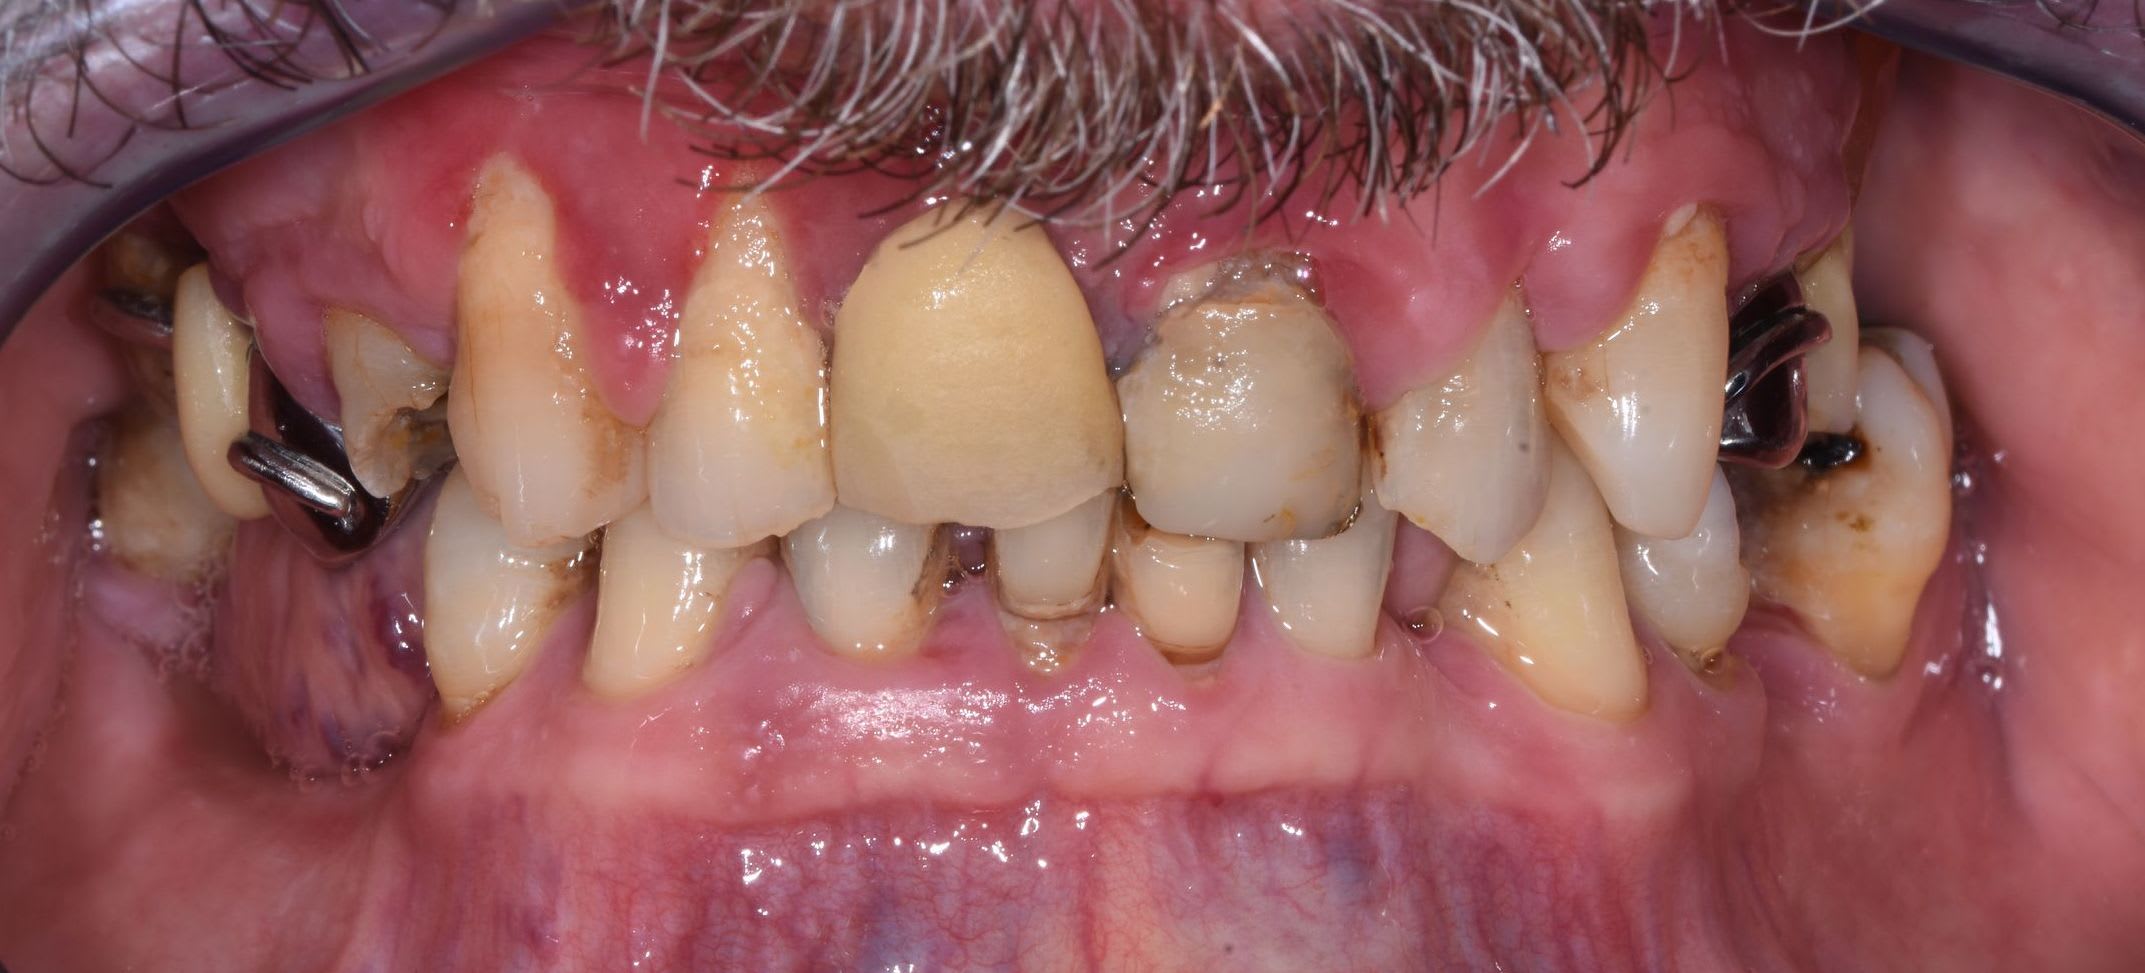

J'ai un patient de 60 ans, bonne santé générale. Rémission de maladie auto-immune lourde mais stable depuis 3 ans. Non fumeur.

La première consultation, il y avait de la plaque partout.

Sa demande : garder tout ce qui est possible.

Une motivation au brossage, un det et un surfaçage + tard, histoire de remettre les choses en état, je me retrouve avec ce type de gencive : voir les photos.

tu as remarqué comme le bas est moins altéré que le haut ? pb occlusal majeur .

Des papilles hyperplasiques au delà de leur position physiologique et un rapport dentaire-os 1/2. Tu dois taper dedans à la turbine pour ramener l’ensemble à plat. Raccourcir tes chicots. Mais avant calage postérieur ++++, sans ça, ne rien toucher. Là, c’est de la dentisterie de guerre.

Tu as des migrations secondaires et une dv effondrée, tu ne peux que coiffer au moins toutes les maxillaires entre autre pour rétablir un angle I/i correct, et des courbes compatibles.

Sinon il reste 8 dents au maxillaire. Ya la racine de 11, la 24 qui ont degagé depuis les photos et j'ai raccourci la 15.